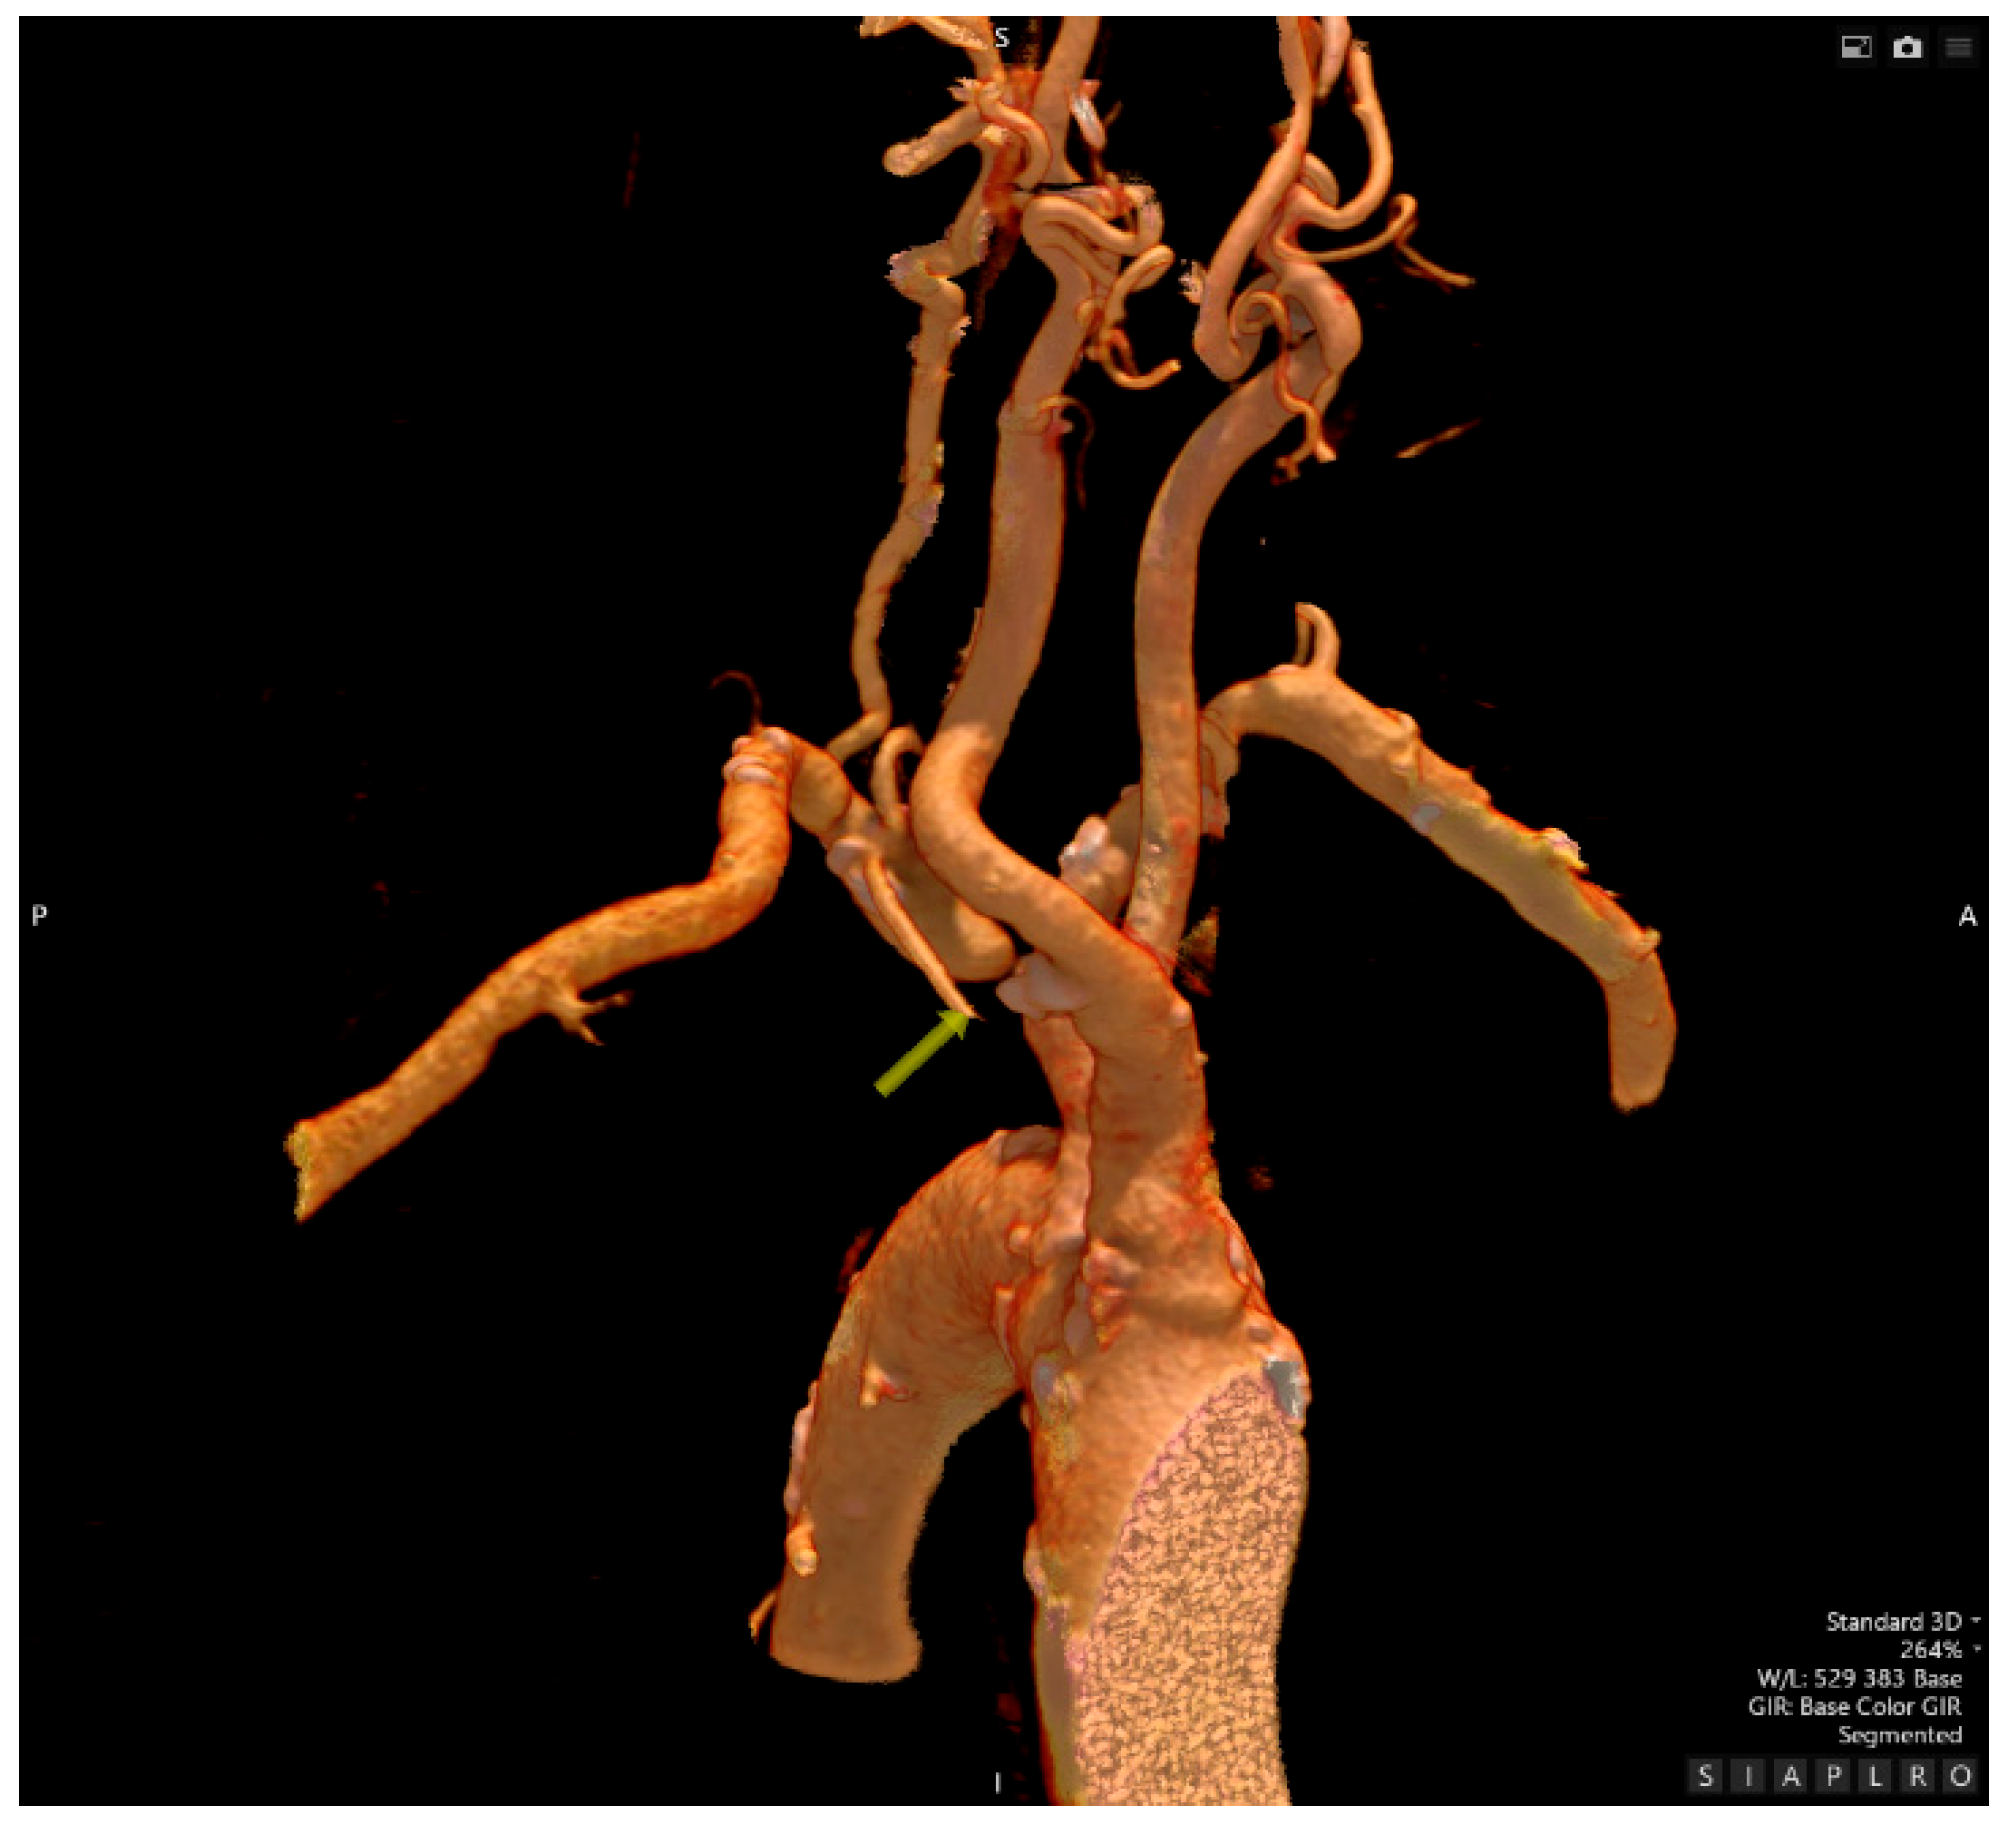

- Computed Tomography Angiography

- Interventional Radiology – an attempt at recanalization of the right subclavian artery